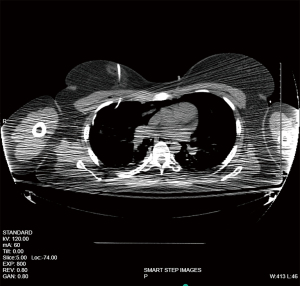

Despite the non-identification of a pneumothorax in the operating room on fluoroscopy (Figure 3), the patient was noted to have a right-sided pneumothorax of approximately 4 cm (about 1.57 inches) on a subsequent upright chest radiograph in the recovery room (Figure 4). The patient did not have decompensation of vital signs, with her lowest oxygen saturation being 94%. The patient did not have major sequelae of this other than to require a pigtail chest tube placed by interventional radiology under the recommendation of a cardiothoracic surgeon consultation (Figure 5). The patient responded well and discontinued the chest tube within 24 hours. The chest tube was removed by the interventional radiologist once they were determined to be stable upon inspection with additional CXRs (Figure 6).

Figure 5 Computed tomography-guided pigtail insertion by interventional radiology.